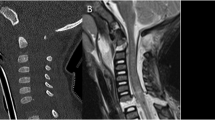

An orthosis for a C5 complete tetraplegic providing active extension and pronation of the forearm is presented. It overcomes and prevents the occurrence of the flexed and supinated C5 tetraplegic arms. Technical data and a case report is included.